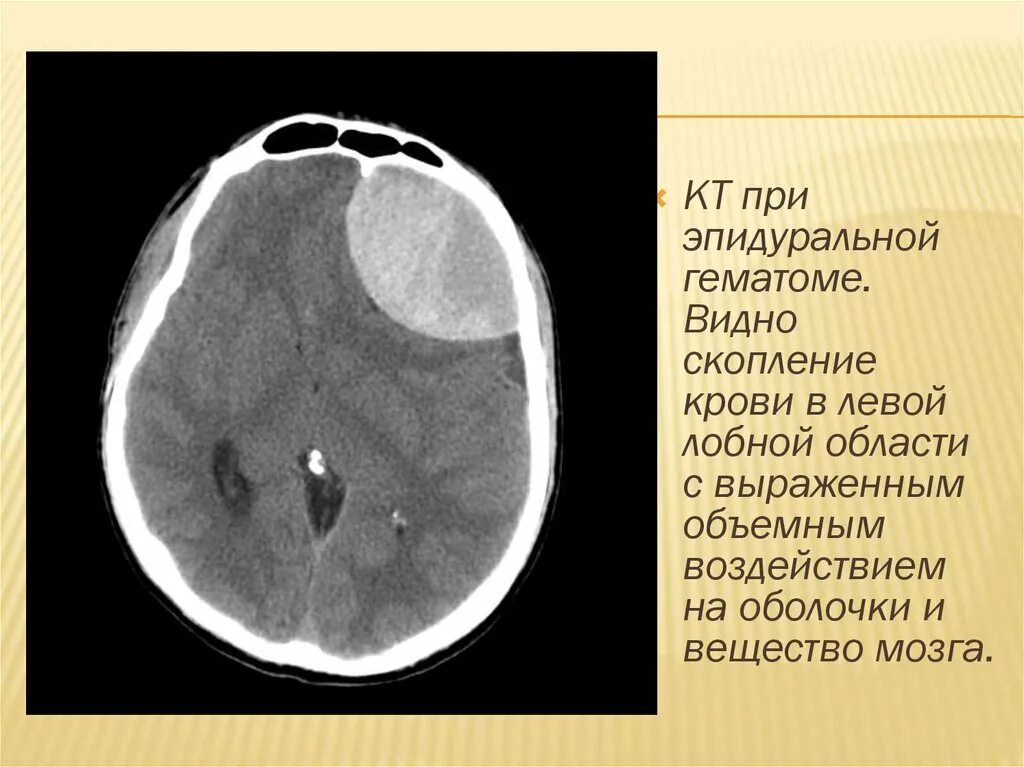

Объем гематомы на кт